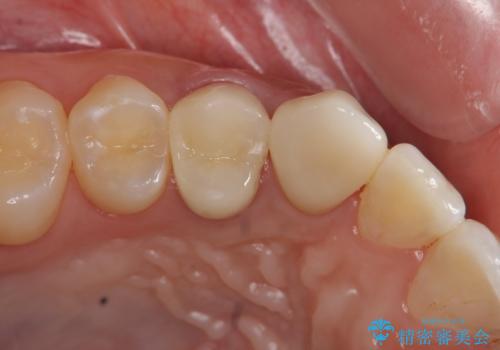

虫歯で歯が折れた セラミック審美修復

ジルコニアクラウンによる咬合機能回復、根管治療を行い歯の痛みをとり長期的な予後の見込める治療を計画します。

- 26万円(仮歯・ファイバーコア・ジルコニアクラウン×2)費用は治療当時の料金となります

一度治療した歯でも、虫歯が再発したりクラウン・インレーの設計が悪いと急に歯が割れたり短期間のうちに悪くなってしまったりする可能性が高まってしまいます。